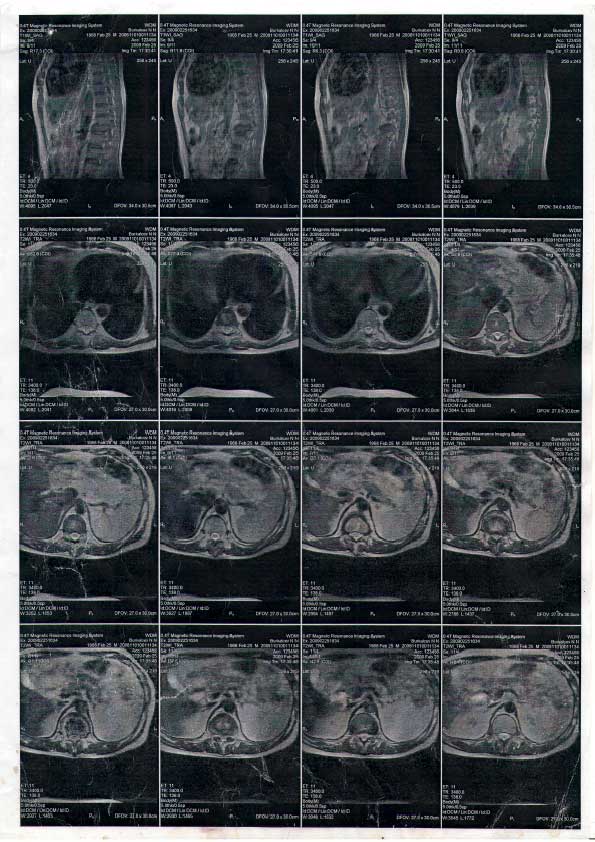

Заключение МРТ: 1 стр. 2 стр. 3 стр. 4 стр.

С 2010 года Коленька постоянно находится в Отделении Трансплантации и Хронического Гемодиализа в Запорожской Областной Клинической Больнице. В настоящее время его мучают сильные боли во всем теле, отнимаются ноги и руки, резкий перепад давления, сердечные боли, головные боли, боль в позвоночнике в области поясницы, боль во всех суставах, сосудистая дистония, постоянные боли в печени и желчном пузыре, боли в желудке, в целом поражены все органы. Участились из-за сахарного диабета диабетические комы, резко падает сахар в крови.